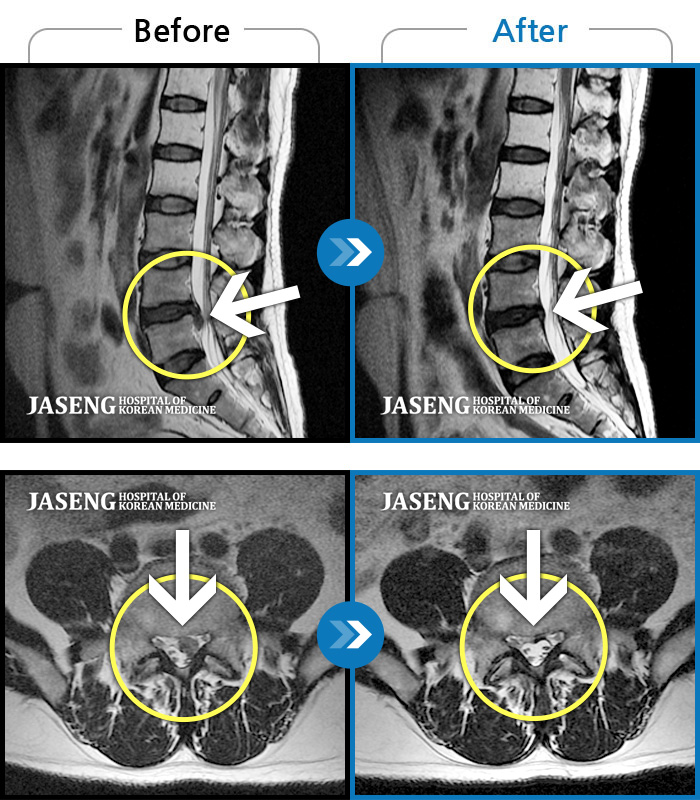

허리디스크

보라매 · 빈상은 원장

엉치에서 좌측 다리까지 통증, 저림으로 움직일 수가 없어요.

촬영시기

2024.08.03 ~ 2025.05.02

2025.12.12

조회수 118